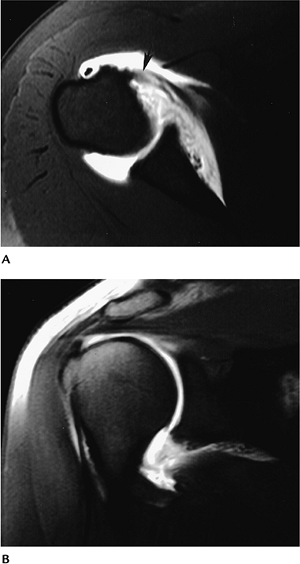

![]() |

FIGURE 7-26 Axial MR image demonstrating the types of capsular attachment (broken lines): Type I at glenoid margin, Type II just medial to margin, and Type III more than 1 cm beyond the glenoid margin.

P.480

FIGURE 7-27 Axial MR arthrogram image in a patient with prior anterior dislocation. There is stripping of the anterior capsule (white arrow) and a labral tear (black arrow) with a complete subscapularis tear.

Multidirectional instability. Stress arthrogram image after prior anterior repair shows inferior subluxation of the humeral head. |